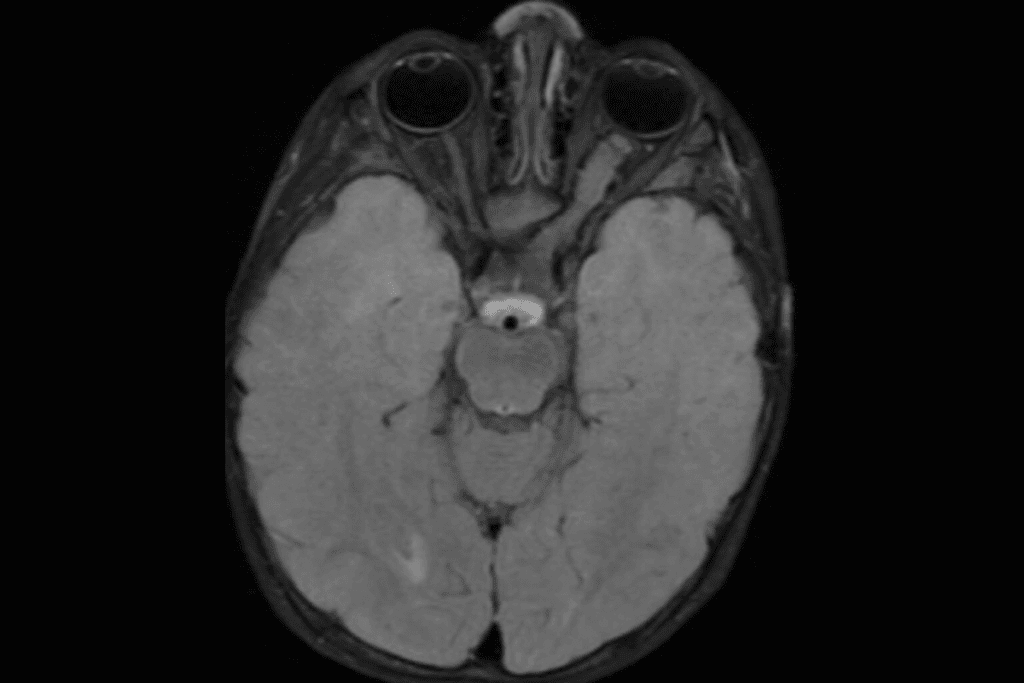

Glioblastoma Prognosis and Survival Statistics

Glioblastoma is the most aggressive brain tumor, classified as Grade IV. It has a poor prognosis, with a median survival time of about 15 months after diagnosis. Despite aggressive treatment, the 5-year survival rate is less than 10%.

Treatment for glioblastoma often involves surgery, radiation, and chemotherapy.

Grade IV Tumors (Glioblastoma)

Grade IV tumors, known as glioblastomas, are the most aggressive and malignant type. They grow quickly and have a high chance of coming back. Glioblastoma is one of the toughest brain cancers to treat.

The outlook for glioblastoma patients is poor, even with new treatments. Research is ongoing to improve treatment outcomes for this aggressive tumor type.